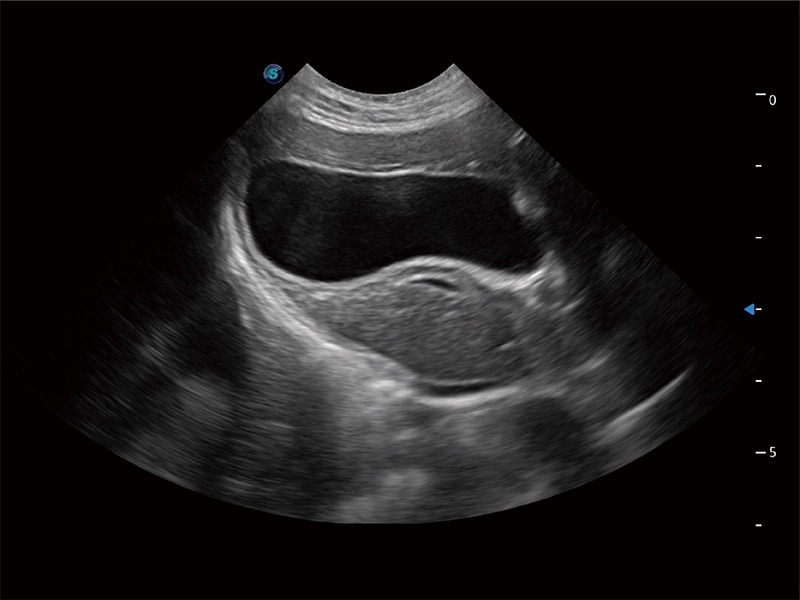

动物是人类最亲密的朋友和最值得信赖的伙伴。16877太阳集团也一直致力于探索动物专用的超声影像解决方案。全新推出的ProPet系列,是16877太阳集团在动物超声影像智能化、专业化、精准化的一次跨越式革新。动物不能用言语来表述自己的不适,通过超声影像,ProPet系列搭建了动物医生与不同物种沟通的“桥梁”,为动物医生注入了“治愈之力”。 ProPet 80 是16877太阳集团匠心打造的一款高端动物专用彩超,采用性能卓越的全新硬件架构,极大提升超声系统的运行效率和数据处理能力,帮助动物医生从容应对日益增多的挑战性病例和日益多样化的临床需求。

高性能和先进的临床应用工具可以为动物医生提供临床信心。ProPet 80 搭载了先进的腹部和浅表应用工具,帮助医生在日常临床实践中发挥前所未有的作用。

ProPet 80 全新的动物超声智能软件和丰富的探头群,为动物医生提供了高清晰度和精细分辨率的图像,无论在宠物、马科、畜牧还是实验室动物等应用中都可以轻松应对,为您的日常工作带来满意的体验。